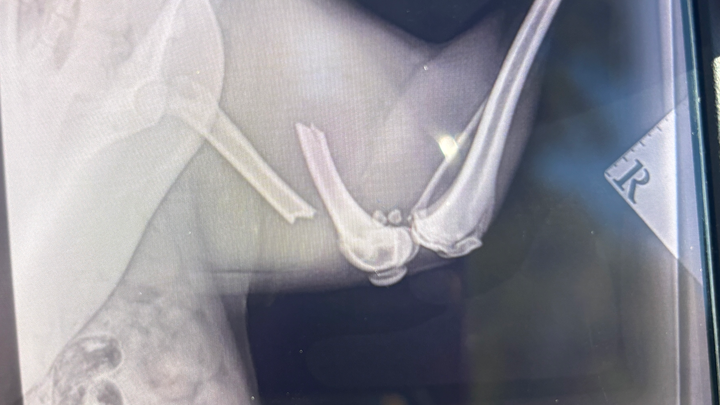

Hi my name is Luna, I broken my FEMA bone on the 23/09/25 and my owner can’t afford the costs to cover the surgery urgently needed.

any donations would be really appreciated to help me recover as soon as possible. It’s hurting being left in this pain.